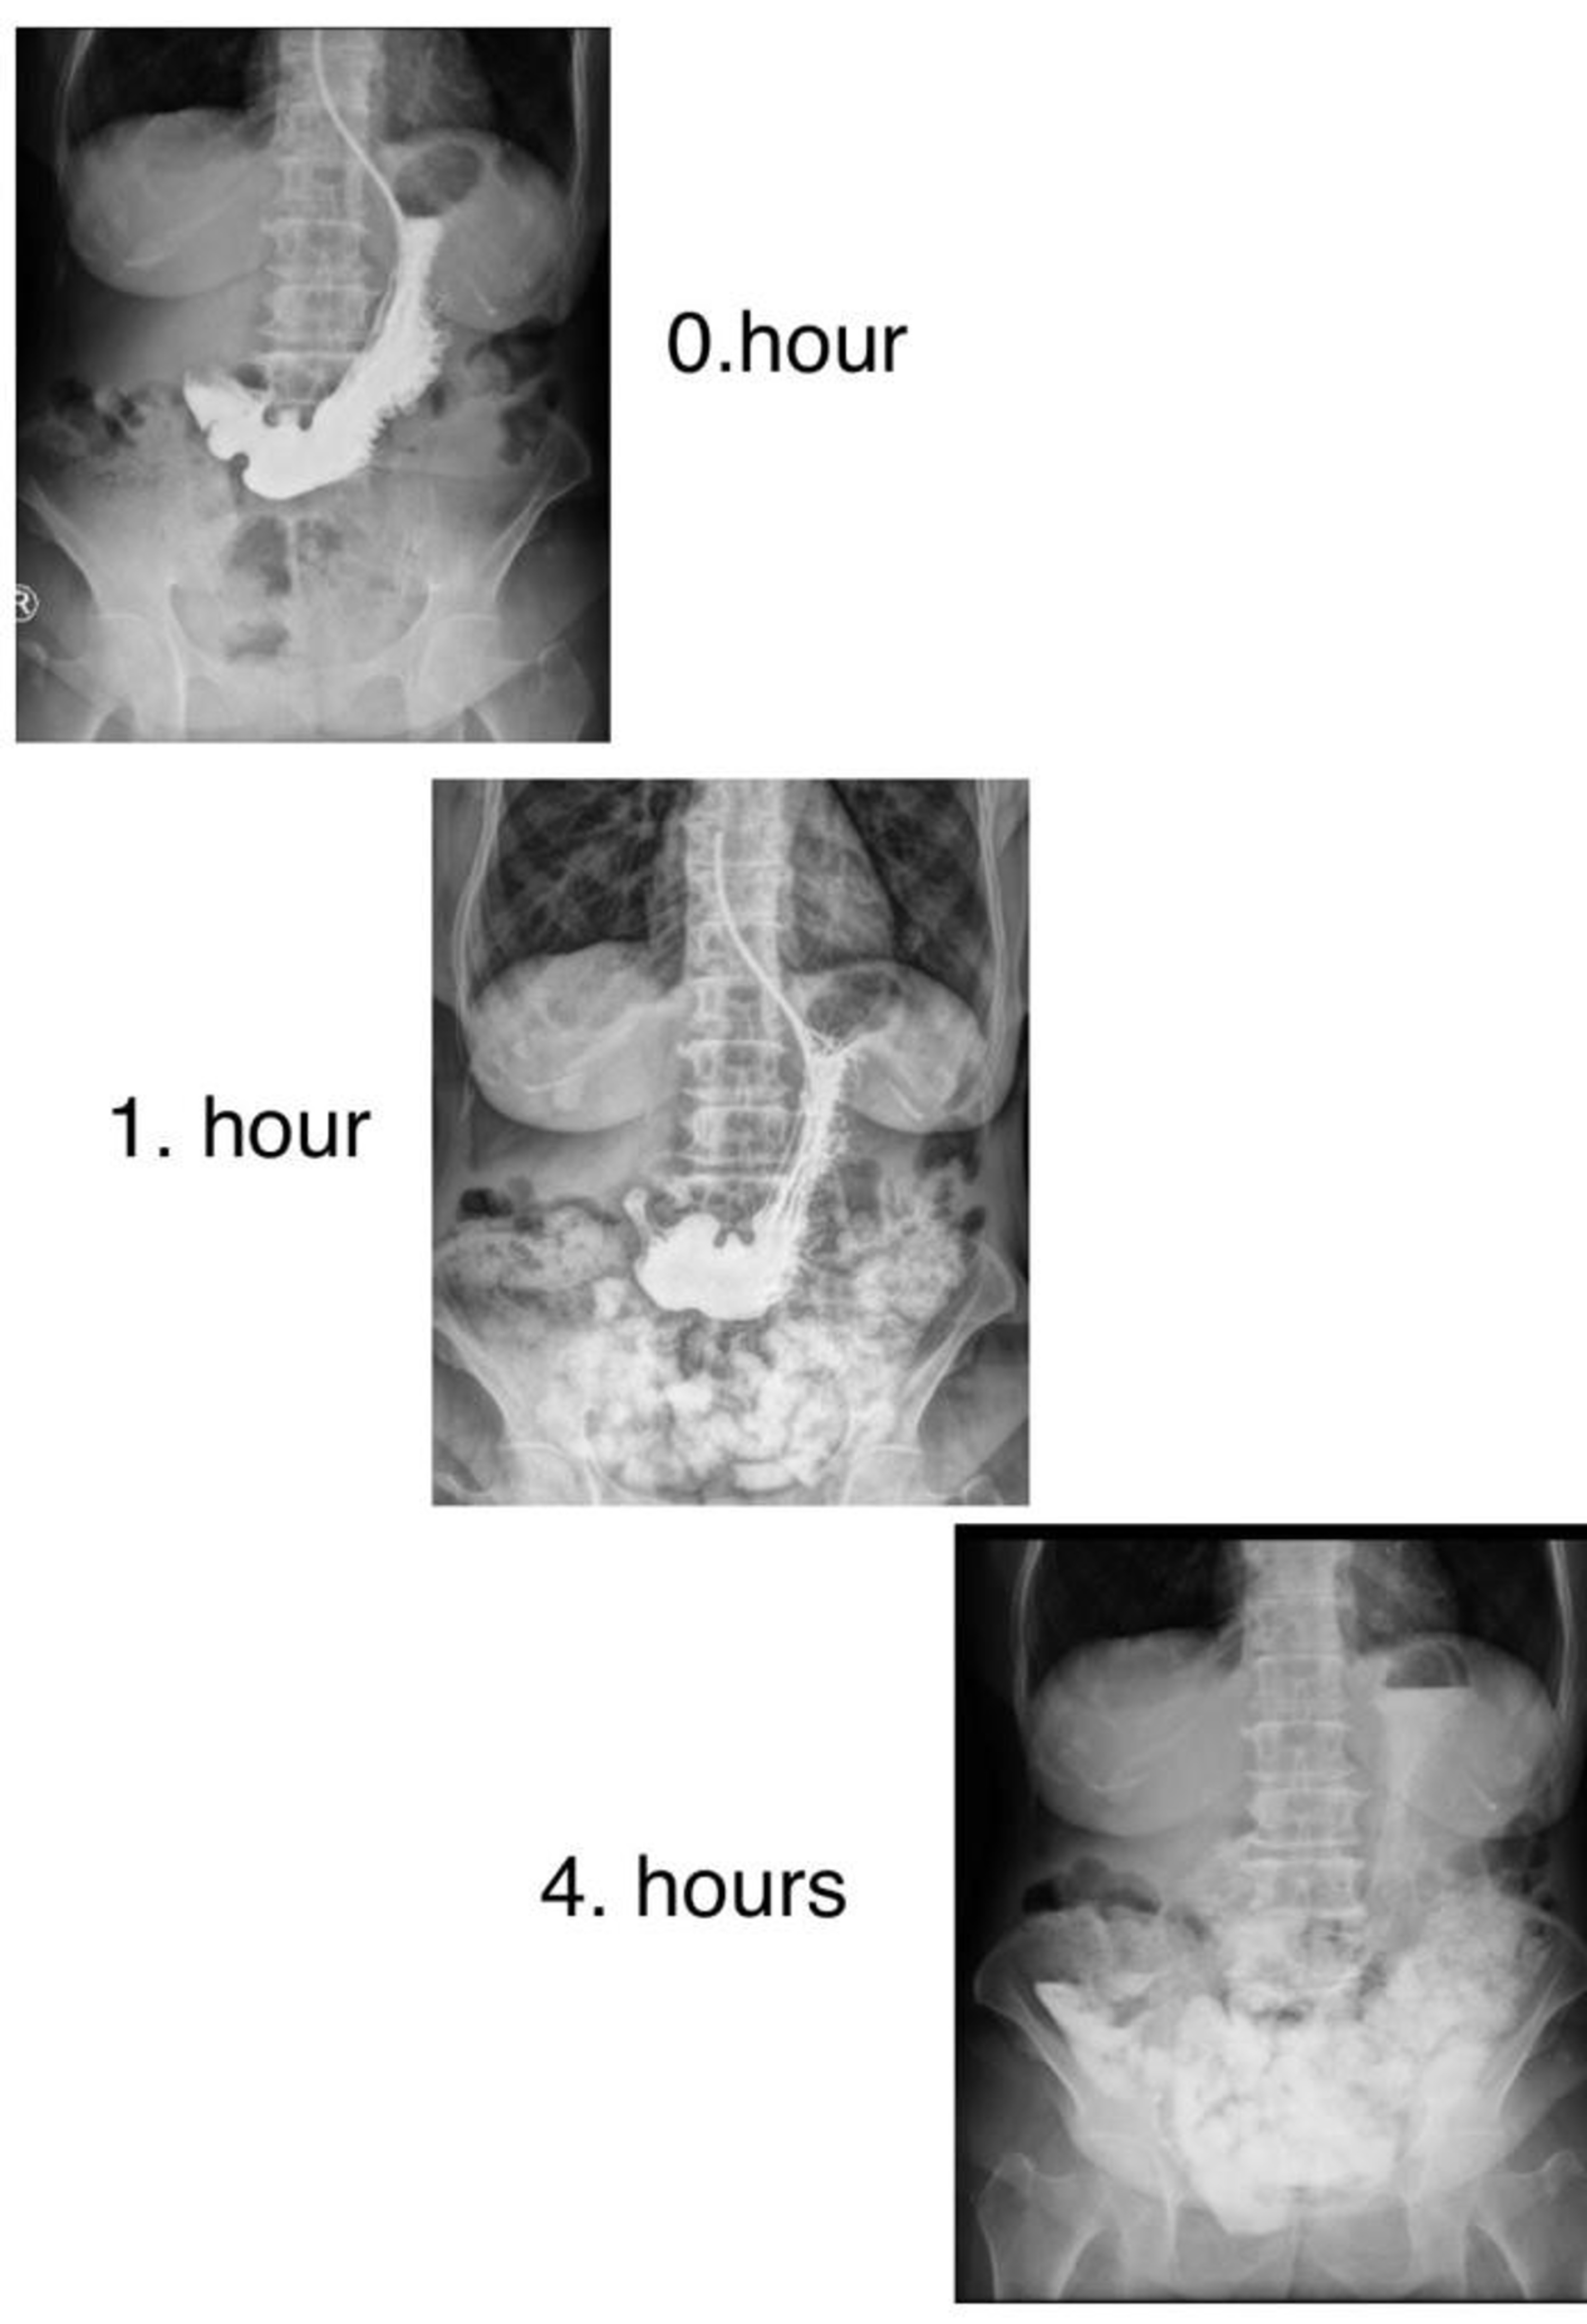

Hospital Follow-up: Oral intake was discontinued, and a nasogastric (NG) tube was inserted. Intravenous isotonic fluids were administered. 30 mg of metoclopramide was started. Due to the patient’s diabetes and lack of oral intake, close blood glucose monitoring was performed. A daily 500 cc of solid gastric contents was drained from the NG tube. Since infection parameters were elevated, empirical antibiotic therapy with third-generation cephalosporins was started. Oral contrast was administered, and abdominal dynamic contrast imaging (ADBG) was performed at 0 and 4 hours (Figure 3). The contrast was seen in the progress to the colon. After the NG output decreased to under 100 cc, the tube was removed on the third day of hospitalization. With a decrease in symptoms, oral intake of liquids was initiated on the fourth day. Solid foods were introduced two days later as the patient tolerated liquid food, and abdominal pain improved. The patient was discharged on the sixth day with recommendations to continue 30 mg of metoclopramide daily and to increase meal frequency.

In one case, a barium study showed a decreased gastric emptying rate and gastric dilation.4 In another, a barium radiologic examination revealed the absence of esophageal peristalsis, gastric dilation, and solid food remnants.5 In a case reported by Tonzi et al., after no improvement with frequent and small meals, an endoscopy was performed, revealing an incompetent lower esophageal sphincter and undigested food particles in the stomach, leading to the diagnosis of diabetic gastroparesis. In our case, abdominal CT angiography showed a distended abdomen with dense content, and no further tests were performed since gastroparesis was suspected based on the CT findings. Dynamic contrast imaging was used to observe the progression of contrast through the gastrointestinal system.

Figure 3. Direct radiography image at 0., 1. and 4. hours after oral contrast